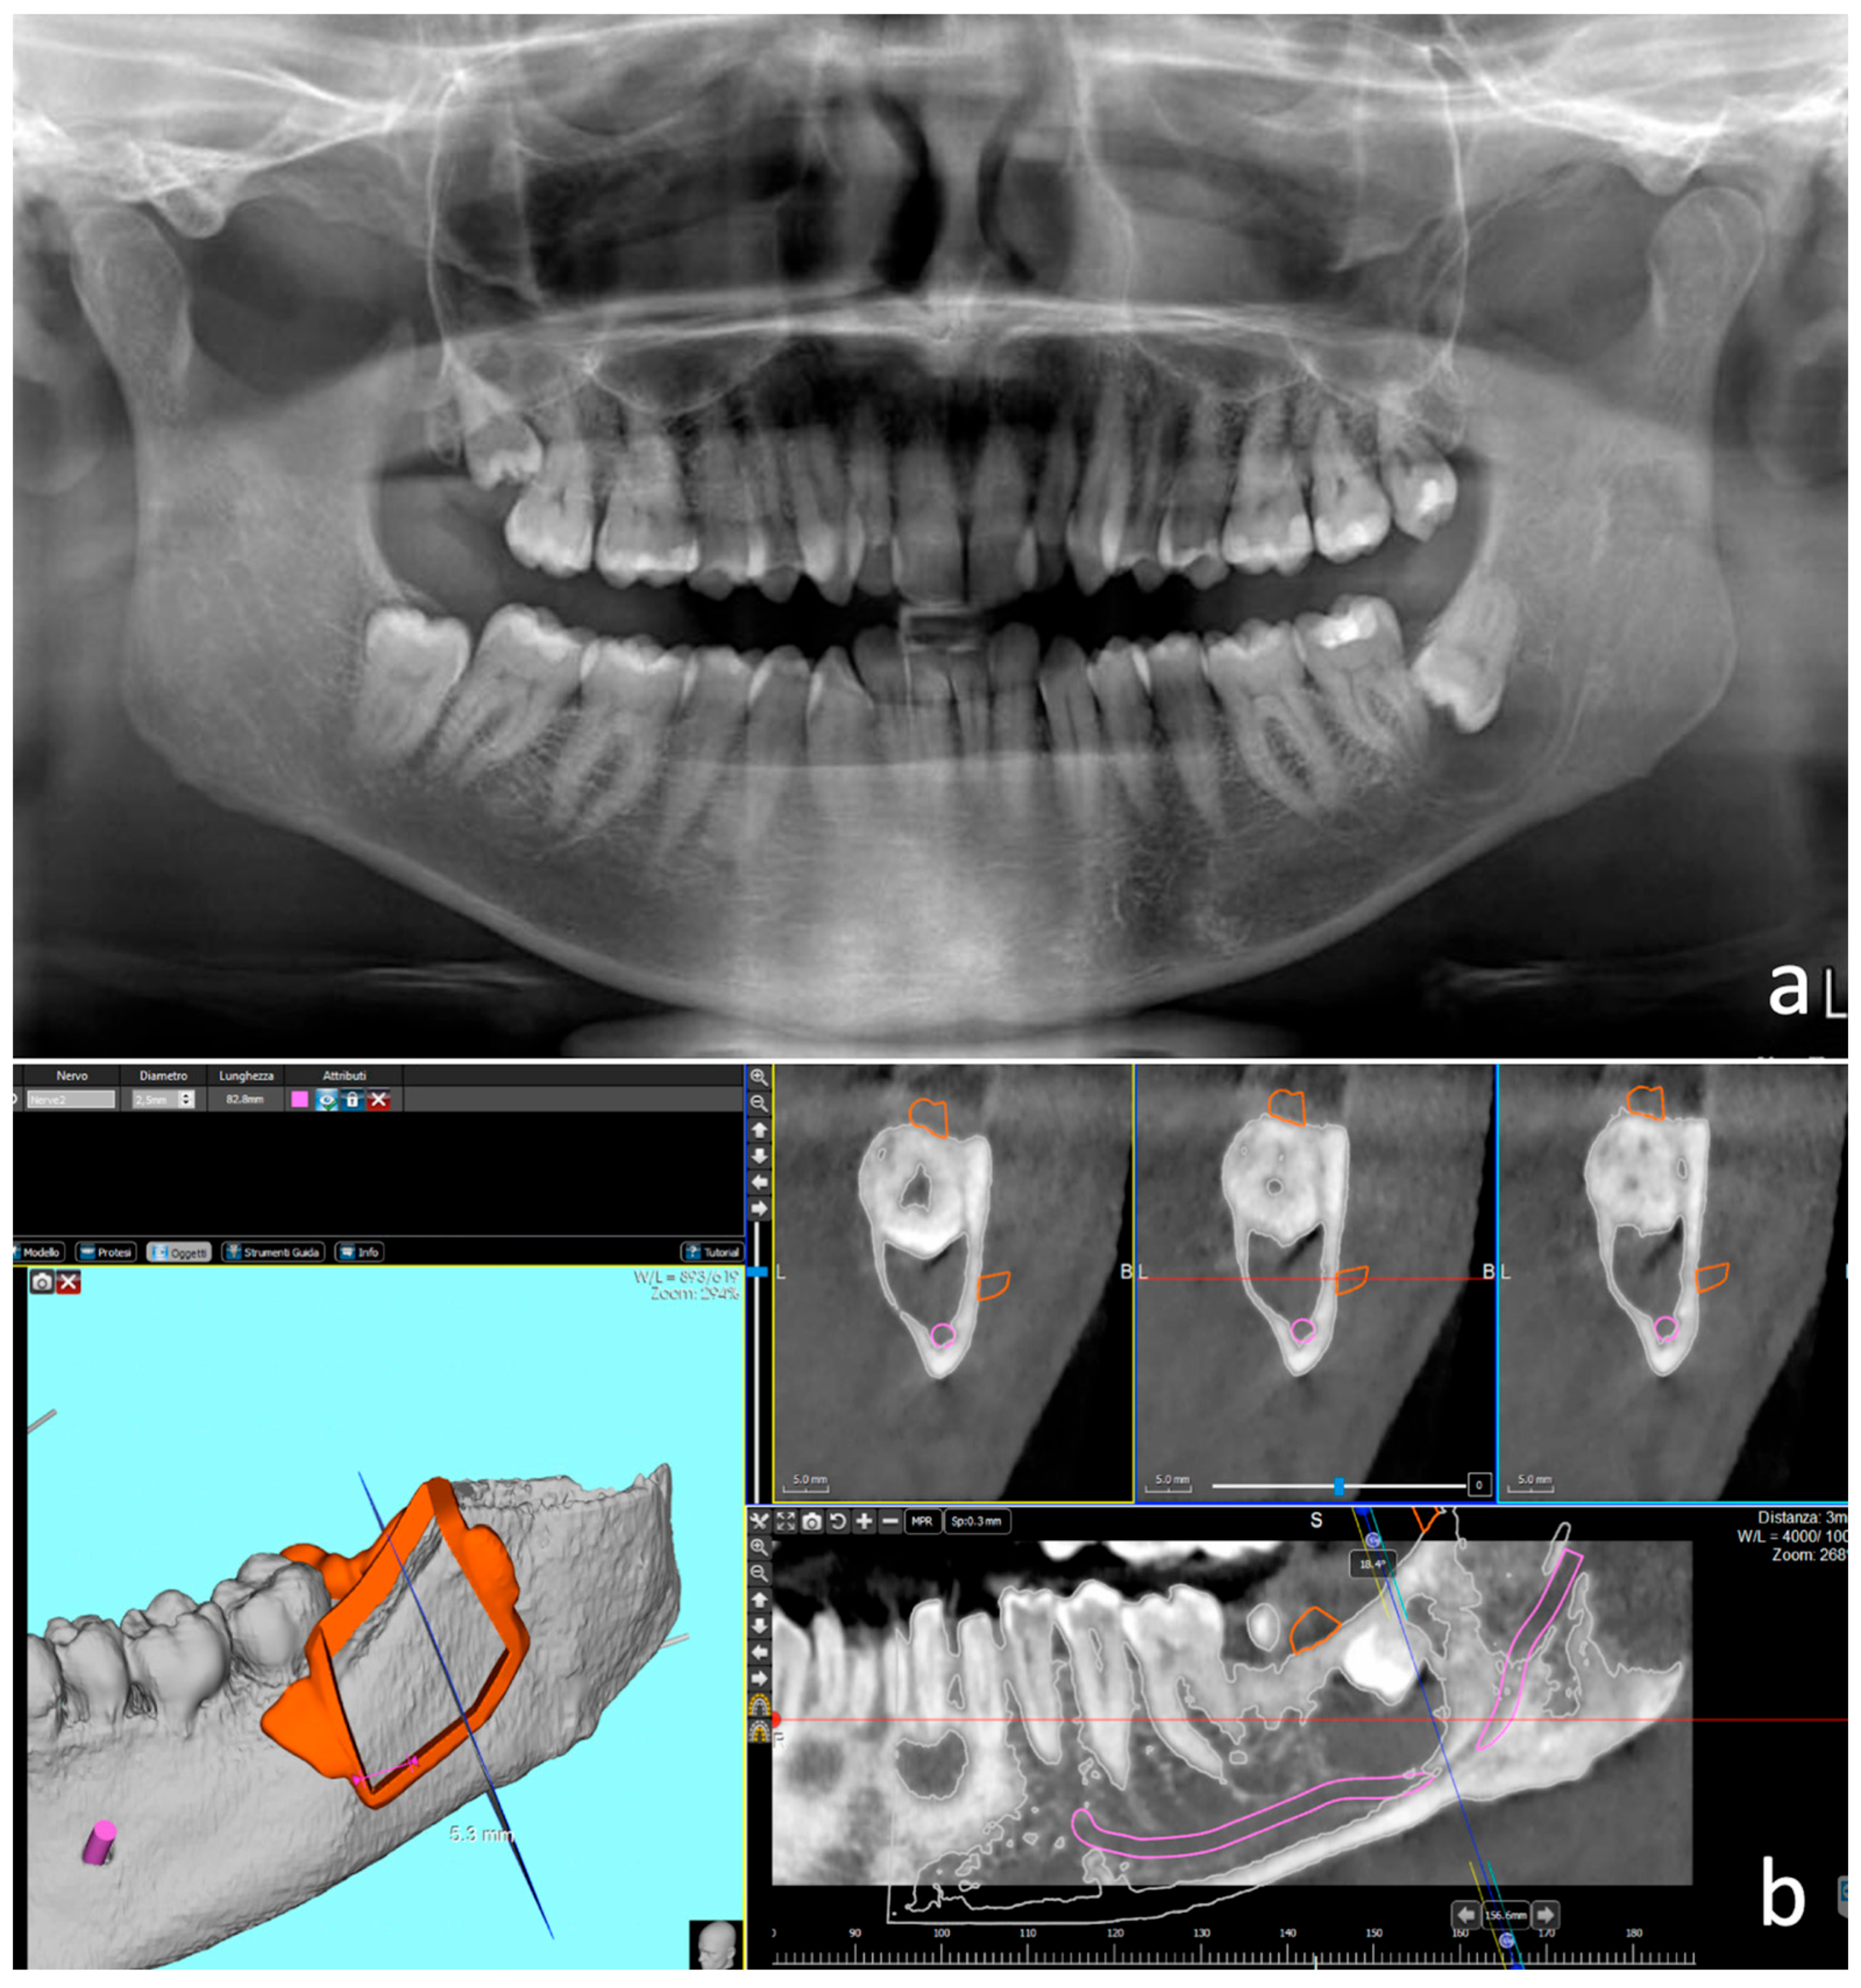

2. Description of the Cases